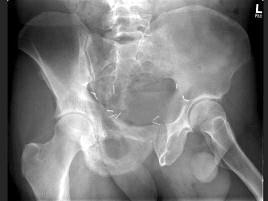

问题 男,56岁,右髋部疼痛,5年前被确诊为前列腺癌,结合图像,最可能的诊断是?(?)

选项 A.骨纤维异常增殖症 B.转移性骨肿瘤 C.畸形性骨炎 D.内生软骨瘤 E.非骨化性纤维瘤

答案 C